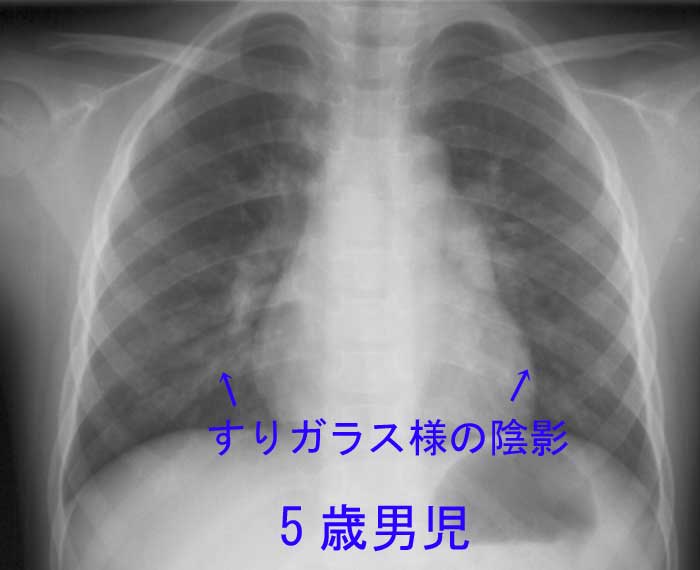

気管支炎が肺炎になると、通常、症状が悪化します。粘液を伴う咳や発熱がみられます。医師が患者の症状に基づいて肺炎を診断できない場合、胸部X線検査または血液検査を提案することがあります。